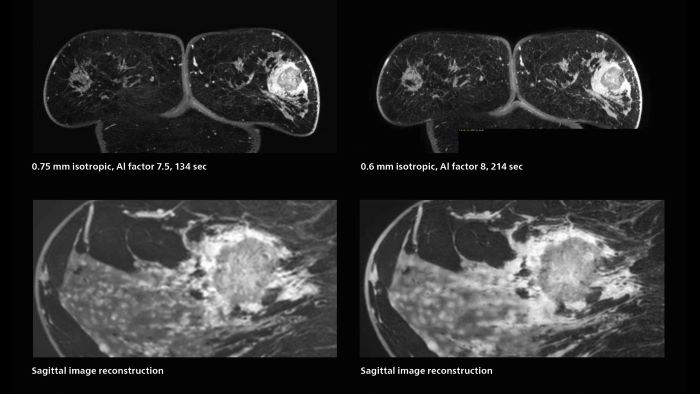

Speed and high image quality are also important factors determining the diagnostic value of breast MRI. “When the spatial resolution is not high enough for making the diagnosis of breast cancer, a very difficult decision must be made,” says Dr. Katahira. “Since SmartSpeed now allows us to increase the resolution, we can often easily provide a confident answer. In the past with SENSE we used 1.2 mm isotropic voxels in breast imaging after contrast admission. With Compressed SENSE that is 0.8 mm. Now with SmartSpeed we can acquire 0.6 mm isotropic voxels and the images are so clear that even tiny details are clearly visible.”

3D MRI of breast cancer

Scanning was performed with two different voxel sizes. AI enabled volume MRI allows image reconstruction in other directions. Biopsy revealed invasive ductal carcinoma in this patient. Performed on Elition X.

Fast AI-enabled MRI of breast cancer: comparing 3D acquisitions with 0.75 mm and 0.6 mm isotropic voxels.

The hospital’s routine ExamCards for breast imaging include:

• ExamCard for 0.7 mm isotropic, 2:09 min, acceleration factor 7.5

• ExamCard for 0.6 mm isotropic, 3:37 min, acceleration factor 8